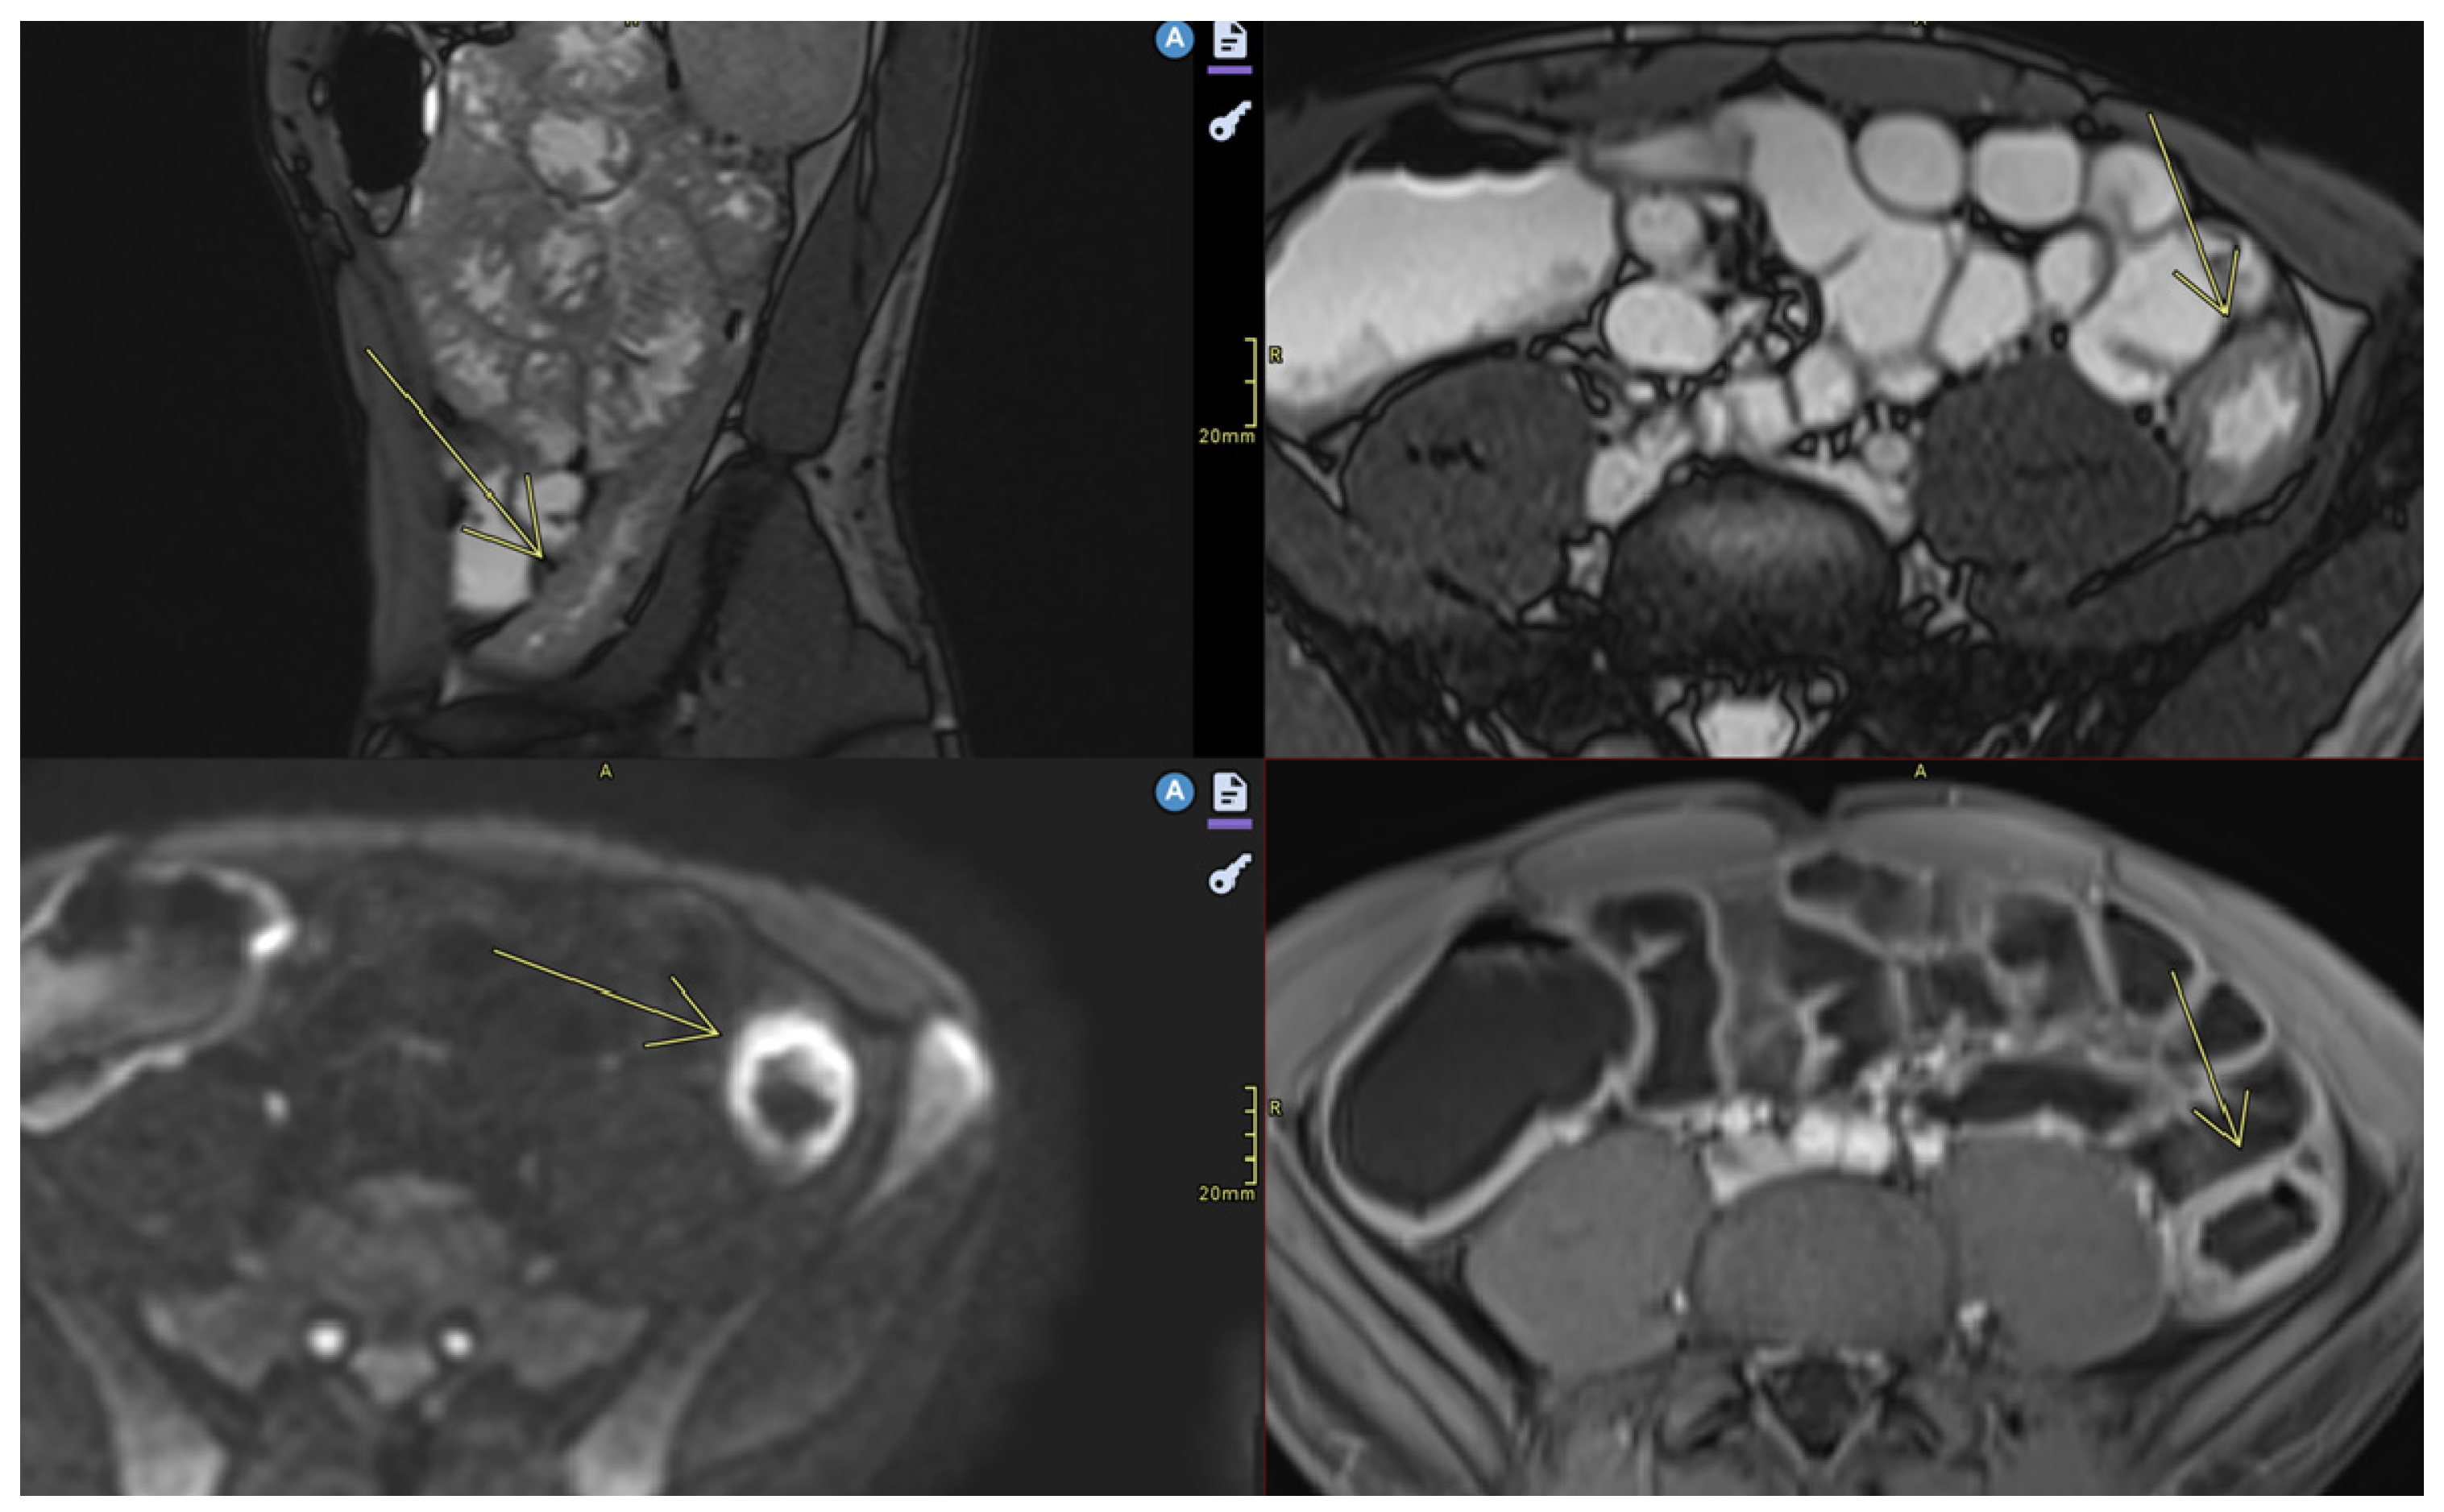

- Fistulas

- Abscesses

- Abscesses are found in the abdominal cavity, intestinal wall, or perianal area [8].

4.2. Screening/Detection of Complications

- ➢

- Enteroenteric, enterocutaneous, and perianal fistulas: MRE can distinguish between simple and complicated fistulas, guiding the decision between conservative treatment and surgical drainage;

- Intra-abdominal abscesses;